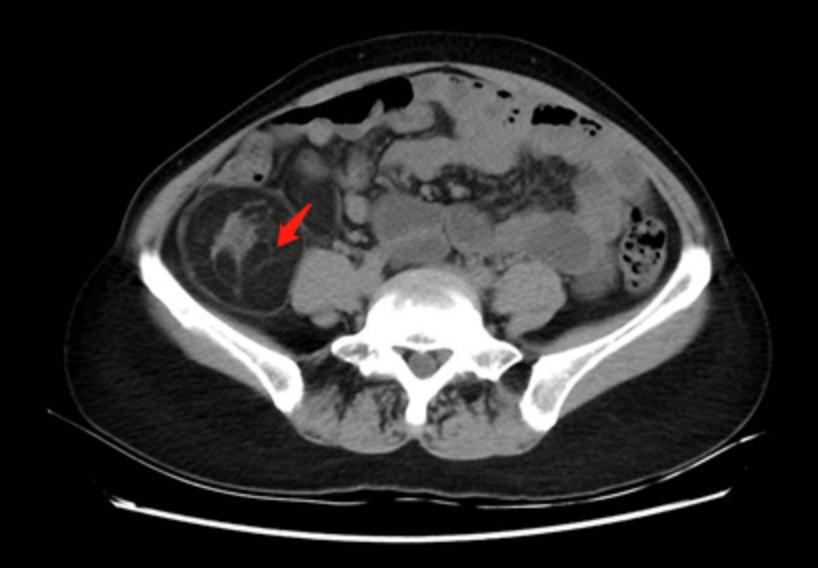

辅助检查:我院腹部CT(肿物最大直径处截图)。

2019年1月17日右中下腹膜后肿瘤复发(37mm×34mm),肝肾间隙及肝右叶外缘新见多发转移灶(17mm×15mm)。

2019年4月11日右中下腹膜后肿瘤复发(55mm×54mm),肝肾间隙及肝右叶外缘新见多发转移灶(17mm×15mm)。